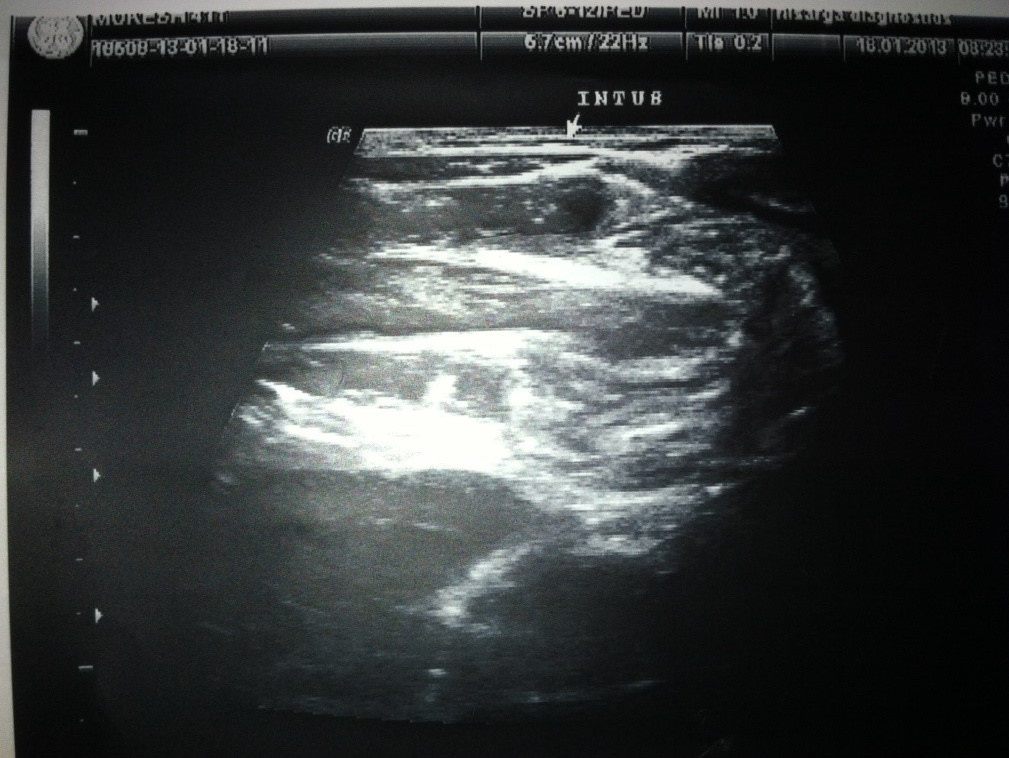

Ultrasonography:

• All patients underwent USG

• Doppler was used to determine bowel ischemia; guides reduction decisions

• Ultrasonography was diagnostic in 93% of our cases

Abdominal ultrasound:

Replaced abdominal radiograph as primary screening modality

• Sensitivity 98 -100%; specificity 88 -100%

• Appearance: outer hypoechoic region surrounding an echogenic center or multiple concentric rings

• Use Doppler to determine bowel ischemia; guides reduction decisions

• Guide hydrostatic and pneumatic reduction